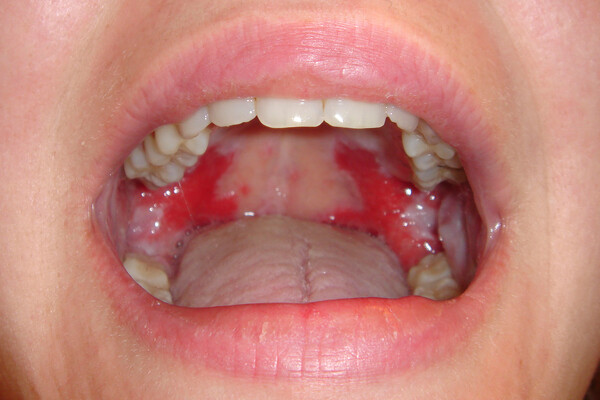

What Causes Red Spots On The Roof Of Your Mouth?

Red spots on the roof of your mouth can be caused by a variety of different reasons. Some are just a minor inconvenience, while others could be a sign of a more serious health issue that may require further investigation. Here are some common possibilities:

Coxsackievirus

The virus behind hand, foot and mouth disease, coxsackievirus can cause painful blisters and red spots on the roof of the mouth, as well as on the hands and feet. It is most common in children under five years of age, but does occur in people of all ages. Treatment options include over-the-counter medications for fever and pain, as well as special medicated mouthwashes to help alleviate the discomfort associated with the oral sores.

In rare cases, oral sores or lesions can be a sign of oral cancer, so it is important to have any spots that are painful, cause difficulty in eating or drinking or do not heal quickly checked by your dentist.